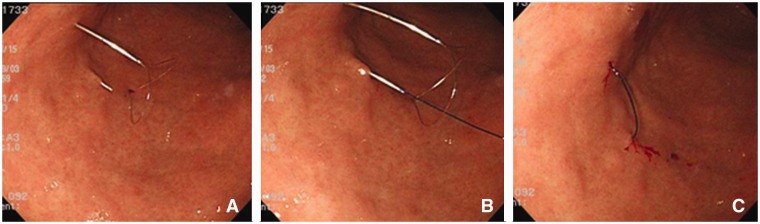

The Funada-style gastropexy device has two parallel, 20-gauge needles and a suture-holding loop (Figure 2). After transillumination, the two parallel needles penetrate both the abdominal and anterior gastric walls. The suture-holding loop is inserted through the first needle. The suture thread is inserted through the second needle and grasped with the snare. The needles are withdrawn and the suture thread is tied on the abdominal wall (Figure 3). In the same way, a second gastropexy is made about 2 cm away.

Figure 3.

Endoscopic view of Funada-type gastropexy. Puncture of two parallel needles and forming a loop to hold the suture (A). The distal end of the suture from one straight needle passes through the loop wire from the other needle (B). The loop is placed back in the needle and the device is pulled out of the body (C). The freed suture is knotted.